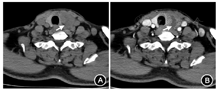

体格检查:体温37.8 ℃,脉搏74次/min,呼吸18次/min,血压153/96 mmHg(1 mmHg=0.133 kPa),体质指数(BMI)24 kg/m2,全身浅表淋巴结未触及肿大,颈部对称,气管居中,无局部红肿,左侧甲状腺Ⅱ°肿大,质地硬,表面不光滑,轻压痛,颈软,吞咽时活动度差,无突眼及双手震颤。入院后查血常规:白细胞9.1×109/L,中性粒细胞76.2%;空腹血糖9.2 mmol/L,餐后2 h血糖15.4 mmol/L,糖化血红蛋白9.0%;超敏C反应蛋白(hs-CRP)20.5 mg/L,红细胞沉降率(ESR)33 mm/h;促甲状腺激素(TSH)0.062 mU/L(参考值:0.55~4.78 mU/L),游离三碘甲状腺原氨酸(FT3)4.9 pmol/L(参考值:3.5~6.5 pmol/L),游离甲状腺素(FT4)18.71 pmol/L(参考值:11.5~22.7 pmol/L),抗甲状腺过氧化物酶抗体(TPOAb)<28.0 mU/L(参考值:0~60 mU/L),抗甲状腺球蛋白抗体(TGAb)20.4 mU/L(参考值:0~60 mU/L),甲状腺受体抗体(TRAb)<0.300 U/L(参考值:0~1.22 U/L);尿常规、大便常规、肝肾功能未见异常。甲状腺超声:甲状腺左叶4.2 cm×3.5 cm×2.5 cm肿物,边界模糊,形态不规整,不均质低回声,肿物与周围组织分界欠清晰;甲状腺单光子发射计算机断层扫描(ECT):甲状腺双叶位置处仅见少量显像剂分布,左叶形态轮廓界限不清,右叶仅见少量显像剂分布,甲状腺整体显像剂摄取明显低于颌下腺(图1);甲状腺增强CT:甲状腺左叶增大,其内团片状低密度影,边界欠清,范围约3.8 cm×3.0 cm,增强后不均匀强化,其内无强化的液化坏死区,双侧颈部多发略增大淋巴结影,增强扫描有强化,考虑甲状腺左叶占位性病变,恶性不除外(图2)。

注:A.甲状腺平扫见甲状腺左叶增大,其内可见稍低密度影(↑);B.甲状腺左叶较右叶增大,边缘不规则,与周围组织分界不清,增强后甲状腺肿物未见明显强化(↑)